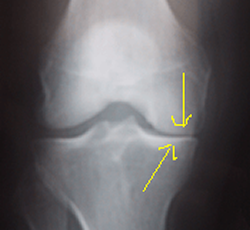

Le Diagnostic de l'arthrose repose sur la RADIO

L'arthrose s'apprécie sur une radio du genou, en position debout (en charge), les genoux légèrement pliés (en position de schuss). La radio permet de mesurer l'espace entre les deux os. Cet espace, l'interligne, correspond à l'épaisseur de cartilage.

Lorsque l'espace entre les deux os, l'interligne articulaire, est moins épais d'un côté du genou par rapport à l'autre, lorsqu'il est "pincé", on parle d'arthrose qui peut être débutante, modérée ou évoluée, en fonction de l'importance du pincement.

++++++++++++++Images radiologiques de l'arthrose

Au début, l'arthrose est le plus souvent partielle, "uni-compartimentale".

Arthrose fémoro-tibiale Interne

Arthrose débutante : petit pincement de l'interligne